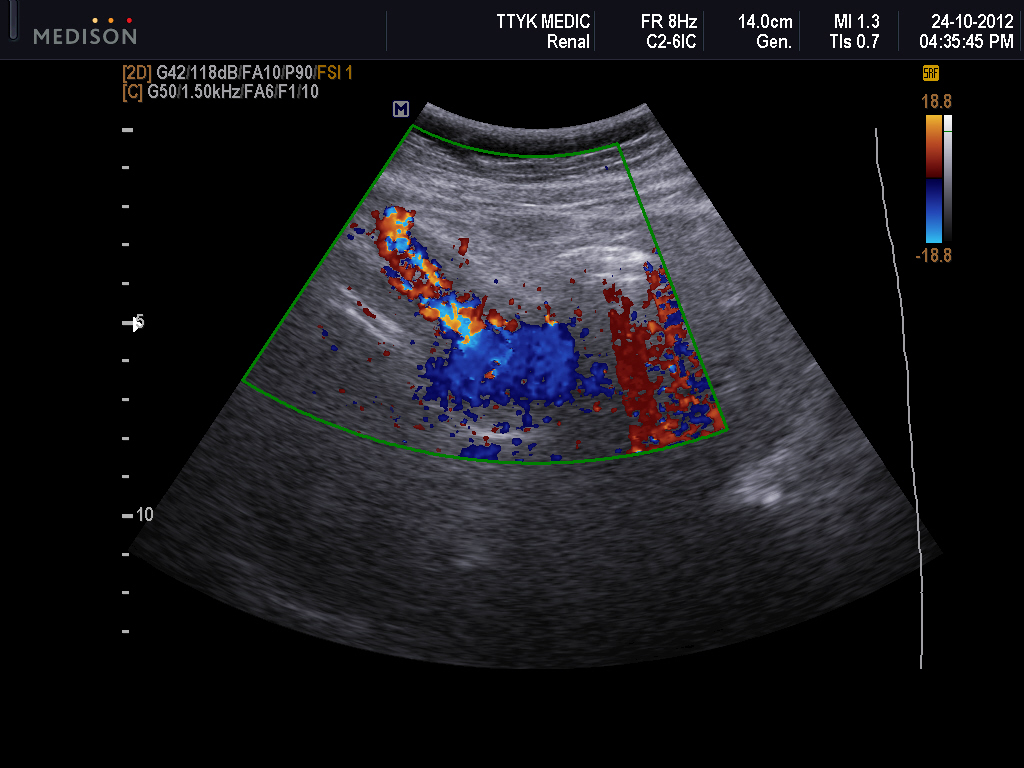

What Does The Color Red Mean On An Ultrasound . we know ultrasound pictures as black and white. red and blue colors on an ultrasound do not mean cancer. what does red or blue mean on an ultrasound? flow that travels away from the transducer (negative doppler shift) is depicted in blue, and flow that is traveling toward the. what do red and blue mean on an ultrasound? warmer colors like red or orange typically represent stiffer tissues, while softer tissues appear cooler with shades of blue or green. They are part of a doppler ultrasound used to assess. Red and blue colors represent the movement of the blood. red and blue are the primary colors in doppler ultrasound to indicate the direction of blood flow. Sometimes, however, you will notice gray shades and red and. In doppler ultrasounds, red and blue colors have specific meanings.